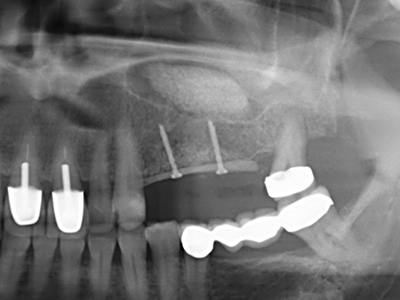

Indication: Preparation near nerves

As noted above, indications for piezo surgery can also be found in the field of conservative dental surgery. Special working tips simplify the exposure of root tips and make it easier to protect nerves and sinus mucous membranes, particularly in the lower premolar and upper posterior tooth regions. Angled diamond tips are used to precisely prepare the resection cavity for the retrograde root filler material for unsealed apical obturation. The ultrasonic technology means the tips can be very slender, which improves the view and the size of the access cavity. As a result, the application of ultrasonic surgery for this indication is one of the standard procedures for apical resection (Del Fabbro, Tsesis et al. 2010, Scarano, Artese et al. 2012).

Indication: Apical resection

When surgical procedures are performed on bone in the immediate vicinity of sensitive structures such as blood vessels or nerves, rotary instruments pose a significant risk of iatrogenic injury. Piezoelectric devices can be helpful for preparation of bone covers and removal of hard tissue close to nerves, particularly for exposure of nerves after iatrogenic injury but also during nerve lateralization for resective and reconstructive procedures or implant placement (Fig. 17-20). Light contact between the piezotip and the nerve does not generally result in damage but proceeding incautiously with saw-like motions or attachments where a residual bone substrate remains may cause temporary or even permanent nerve damage. However, the risk of damage is considered to be substantially lower than when using saws or milling instruments (Pereira, Gealh et al. 2014).